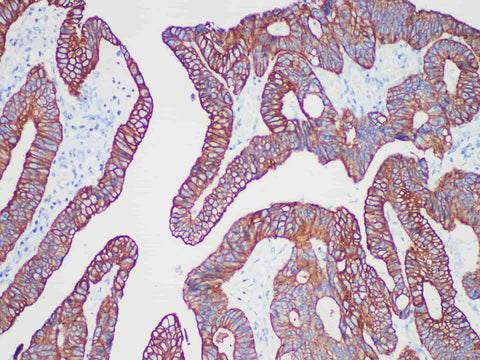

CAM 5.2 Monoclonal Antibody

Applications IHC-P

Tissue Specificity Colon cancer

CAM5.2 is a commonly used very low molecular weight keratin. In normal tissues, secreted epithelium (glandular epithelium) is CAM5.2 positive, while laminated squamous epithelium is negative. CAM5.2 is one of the common markers of glandular epithelium and various adenocarcinomas. Cam5.2 can be used in combination with high molecular weight keratin to distinguish adenocarcinoma from squamous carcinoma. In addition, CAM5.2 is generally considered suitable for the detection of metastatic breast cancer in the (sentinel) lymph nodes.